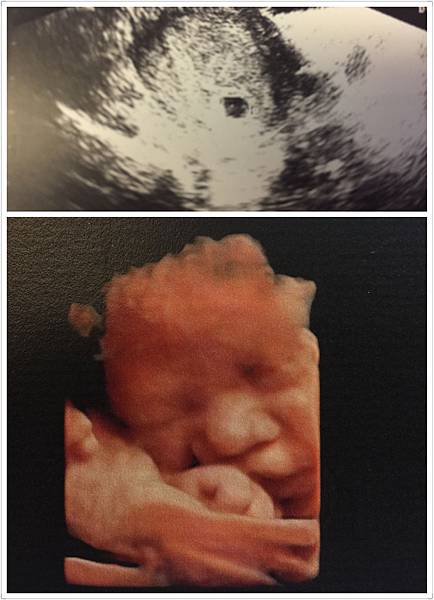

上面是大寶的第一張照片,那天剛好體檢驗到,是一顆小胚胎!

下面是 36周在李木生拍 4D超音波照,超清楚吧! 寶寶正要吃手 哈~ (第一胎2015年)